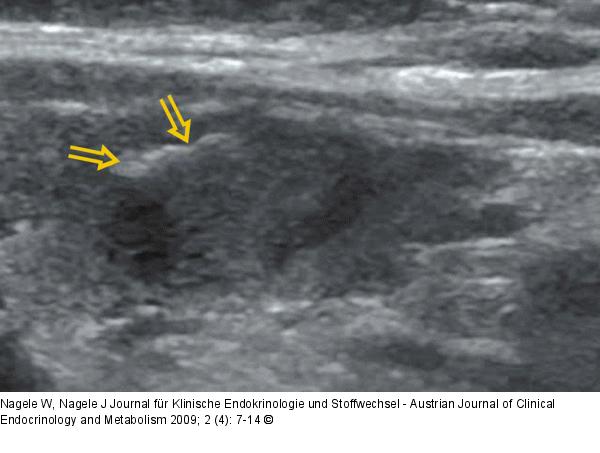

Abbildung 6: Schilddrüsensonographie Schollige Verkalkung in einem echonormalen Schilddrüsenknoten |

Abbildung 6: Schilddrüsensonographie

Schollige Verkalkung in einem echonormalen Schilddrüsenknoten |